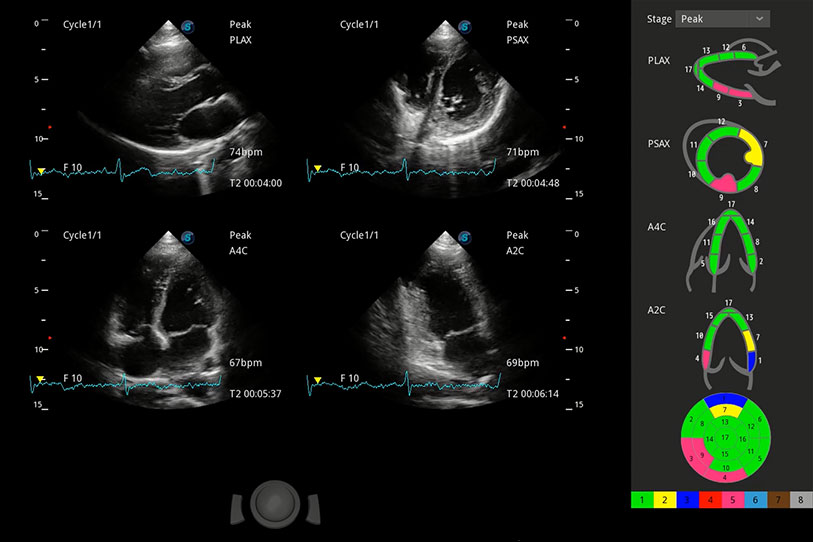

能夠基于左心室壁追蹤和辛普森法,自動計(jì)算射血分?jǐn)?shù),支持多個可移動點(diǎn)描跡,與手動測量相比,極大節(jié)省了動物醫(yī)生的時(shí)間和精力。

具備多種協(xié)議可選,同時(shí)支持17階段劃分法和專業(yè)的SE報(bào)告。

通過360度任意調(diào)節(jié)3條M型取樣線,在同一心動周期上觀察心臟不同位置的運(yùn)動曲線,得到準(zhǔn)確的心功能測量數(shù)據(jù),有效評估心肌運(yùn)動及左心室功能。